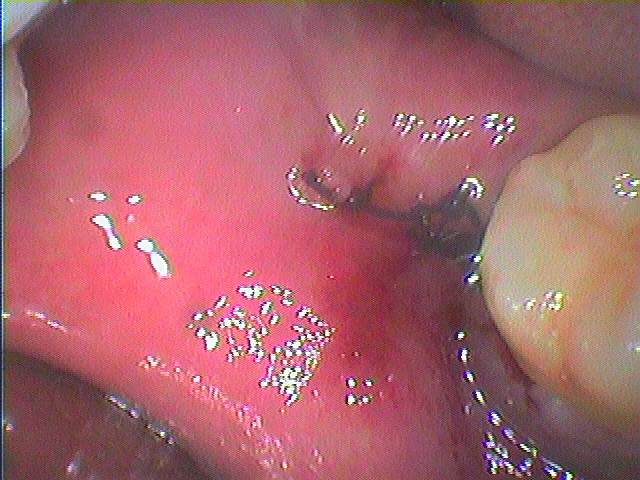

このような玉ねぎみたいな親不知も歯医者泣かせになります。| |広島市安佐南区の歯科医院 このような玉ねぎみたいな親不知も歯医者泣かせになります。 トップ お知らせ・ブログ このような玉ねぎみたいな親不知も歯医者泣かせになります。 このような玉ねぎみたいな親不知も歯医者泣かせになります。 Web診療予約 初めての方へ 選ばれ続ける理由 院内設備について 歯が痛いしみる一般歯科 歯がぐらぐらする歯周病 健康な歯を保ちたい予防歯科 子供の虫歯予防をしたい小児歯科 銀歯をセラミックに審美歯科 白い歯を目指しませんか?ホワイトニング 矯正専門医がいるので安心矯正歯科 抜けた歯を補いたいインプラント・入れ歯 医院案内 スタッフ紹介 メリィハウス歯科クリニックオフィシャルホームページ ラベンダー歯科クリニックオフィシャルホームページ お知らせ・ブログ ホーム 診療科目 一般歯科 歯周病治療 予防治療 小児歯科 審美治療 ホワイトニング 矯正歯科 入れ歯・インプラント マウスピース矯正 初めての方へ 院長・スタッフ 設備紹介 医院案内・アクセス メニューを閉じる